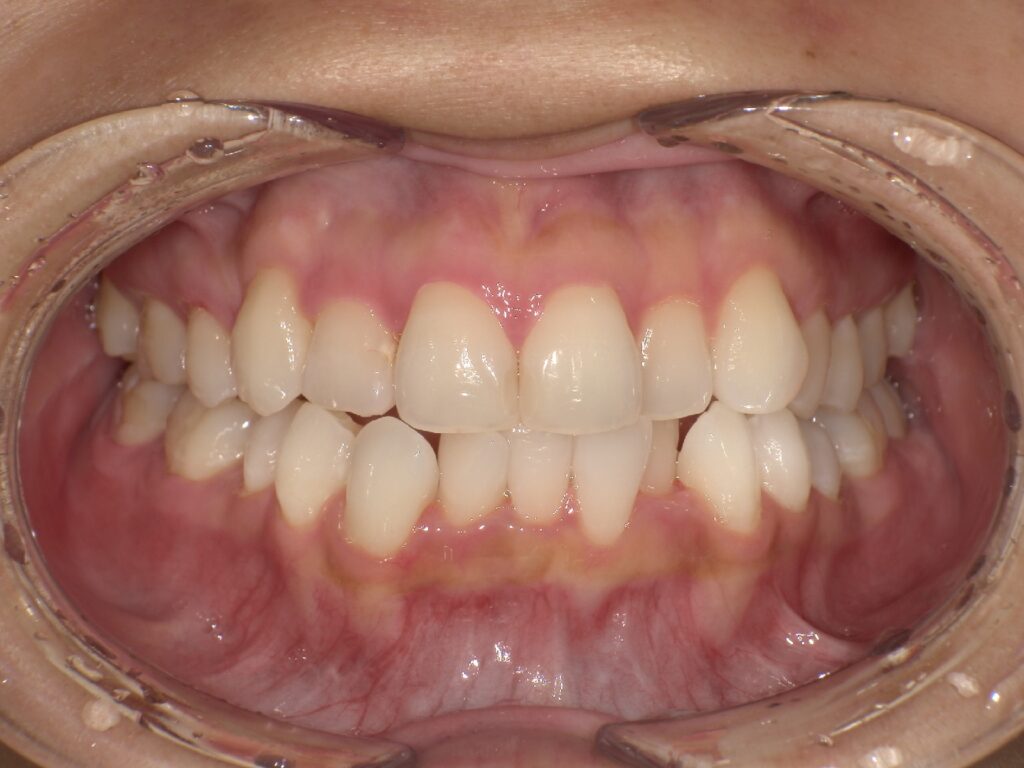

明らかに前歯の突出感が改善し、患者様はこの時点でとても喜ばれていました

矯正治療終了時 部分矯正ということもあり、短期間で矯正治療を終了することができました